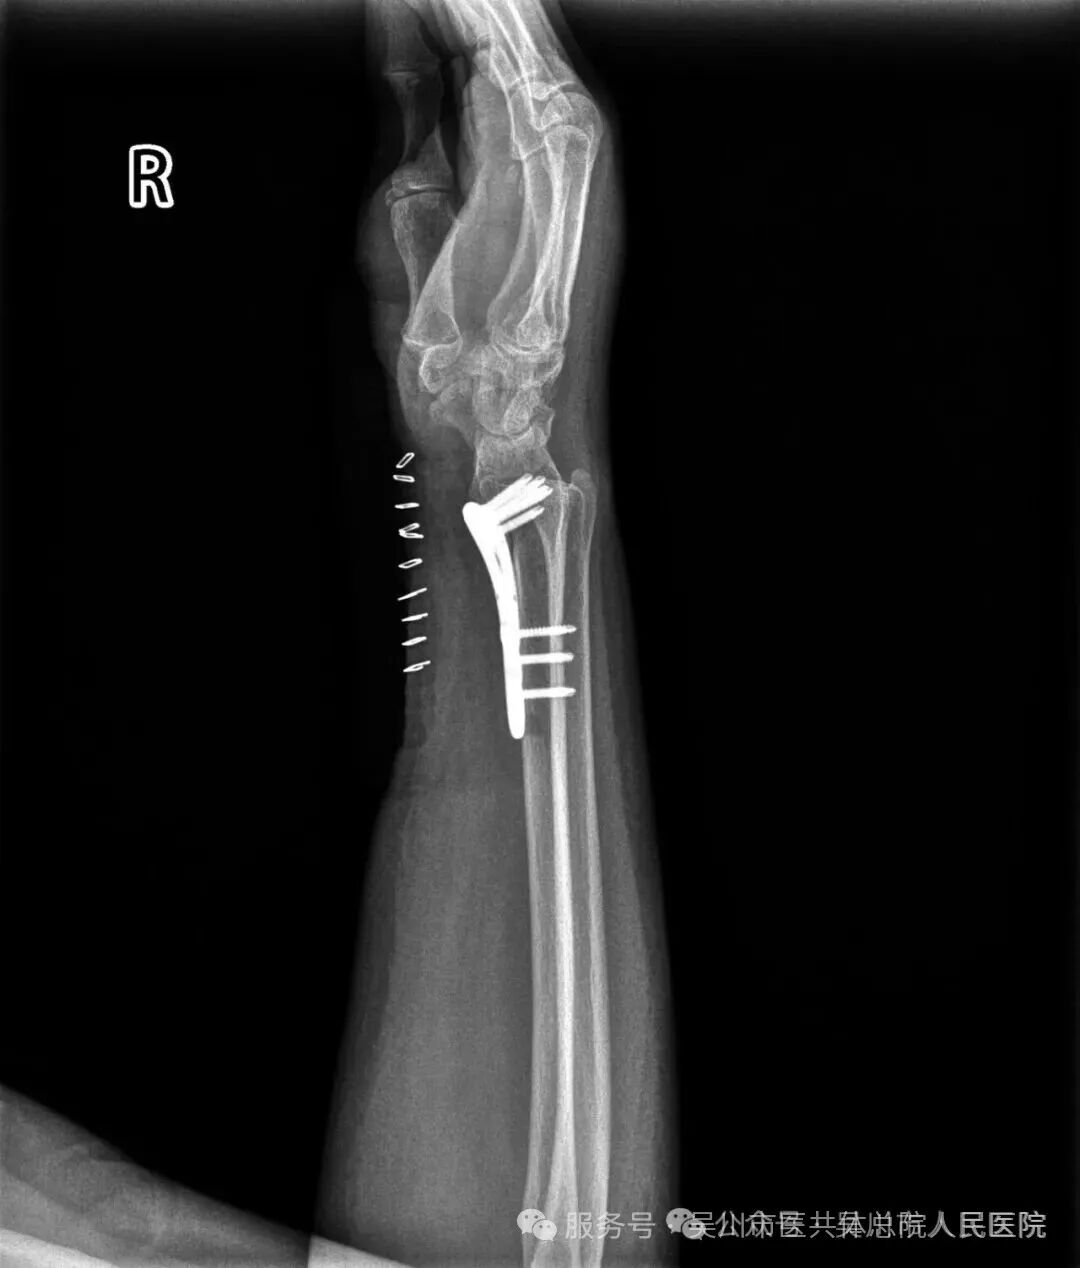

结合潘阿姨的年龄与身体状况,王井旺率手术团队经过缜密讨论,决定采用微创手术治疗方案——依托“百千万工程”专项资助配备的高精度骨折复位设备,在精准定位下实现骨折端解剖复位,再用钛合金钢板进行稳固内固定。该部位骨折若处理不佳,将严重影响手腕功能。面对潘阿姨的病情与忧虑,骨一科团队快速响应,曾文晓副主任医师、欧春云副护士长、王井旺耐心向患者及家属详解病情,舒缓家属焦虑情绪。

为最大限度恢复手腕功能、减少后遗症,经全面术前评估,手术由王井旺主刀。手术当天,无影灯亮起,王井旺手持器械的动作沉稳而精准,眼神锐利如炬,他避开血管与神经密集区域,术中发现潘阿姨骨折碎片存在隐匿性移位,王井旺没有急于操作,而是结合术前影像反复确认复位角度,最终凭借近20年创伤骨科经验,精准调整钢板位置,确保术后关节功能不受影响,这一幕被在场护士记录为“教科书级的手术决策”。整个过程中,护士团队默契配合,精准传递器械,麻醉医生紧盯监护仪上的生命体征,手术室里器械碰撞声与监护仪的滴答声交织成专业的节奏,每一个环节都严丝合缝。

得益于术前精准手术与术后科学护理,潘阿姨的康复进程远超预期。复查结果显示,她的右腕掌屈32°、背伸38°,活动度已接近正常生理范围,日常生活能力基本恢复,不仅能自主穿衣、洗漱,还能重新拿起厨具炒菜做饭。“真的太感谢王医生和护士们了!”潘阿姨的感激之情溢于言表。